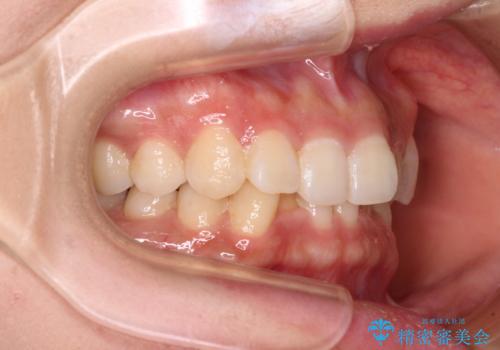

- 前歯のデコボコと深い咬み込みを気にして来院された患者様です。

インビザラインを用いて、前歯の叢生を解消するとともに、深い咬み合わせ(ディープバイト)を改善していくこととしました。

奥歯を後方に直立させることで深い咬み合わせを改善を図り、隠れていた下顎前歯が見えるほどになりました。